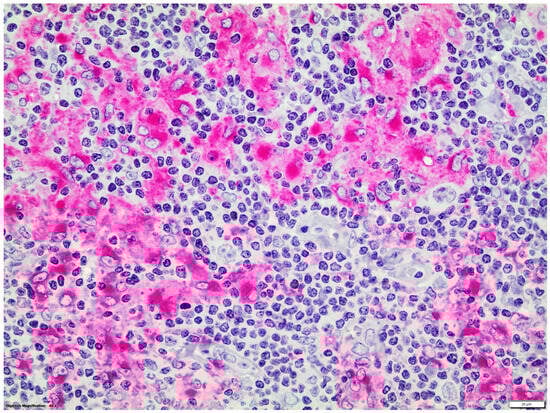

Double immunostainings showed that nuclear GATA3 was expressed by some CD30+ or CD15+ HRS cells and by a few CD3+ T-cells which were frequently organized as small groups, distant from HRS cells. GATA3 nuclear expression was not detected in CD20, CD56 or CD68 + cells (Figure 2 and Figure 3).

Figure 3.

Double LSAB/APAAP immunohistochemical procedure: CD68+ (red staining)/GATA3- macrophages (magnification ×400).